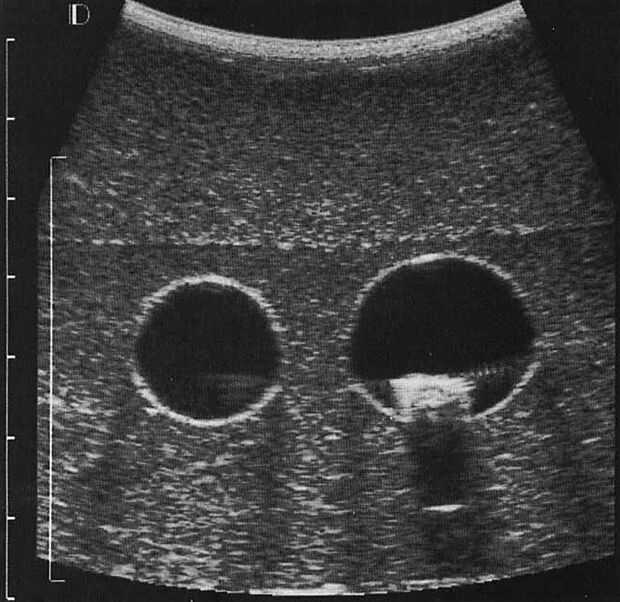

Fantasmas de gelatina requieren gelatina y otros ingredientes que se pueden encontrar en un supermercado local. No son corrosivos, cancerígenos o caro. Hay varios tutorial que sugieren también la adicción de otros materiales orgánicos tales como aceitunas y rigatoni [1] o Metamucil para simular el tejido mamario [2]. El enfoque es bastante sencillo, que utilizas la ración adecuada de gelatina y agua caliente para simular el nivel de rigidez del tejido. Un lector puede consultar [1] para un procedimiento simple y eficaz. Fig.4. muestra la exploración del ultrasonido de una gelatina fantasma.